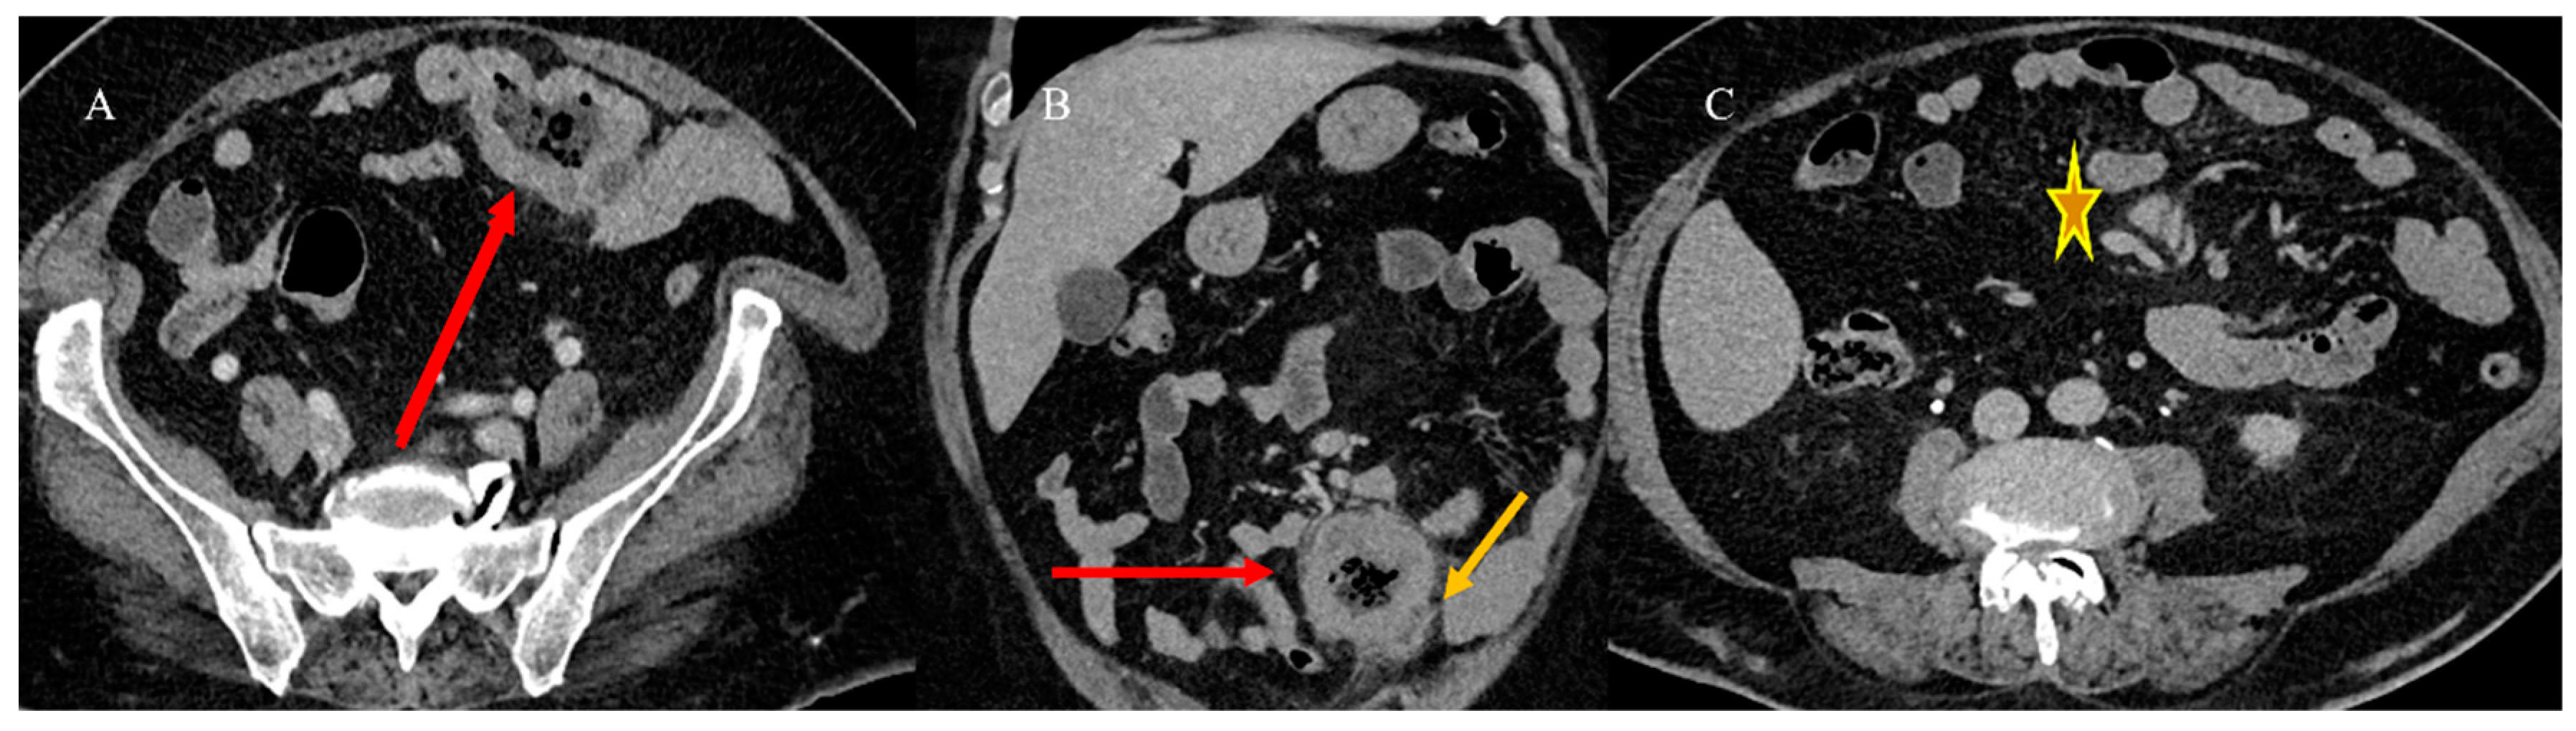

- Marsicovetere, P.; Ivatury, S.J.; White, B.; Holubar, S.D. Intestinal intussusception: Etiology, diagnosis, and treatment. Clin. Colon. Rectal Surg. 2017, 30, 30–39. [Google Scholar] [CrossRef] [PubMed]

- Kim, Y.H.; Blake, M.A.; Harisinghani, M.G.; Archer-Arroyo, K.; Hahn, P.F.; Pitman, M.B.; Mueller, P.R. Adult intestinal intussusception: CT appearances and identification of a causative lead point. Radiographics 2006, 26, 733–744. [Google Scholar] [CrossRef]

- Choi, S.H.; Han, J.K.; Kim, S.H.; Lee, J.M.; Lee, K.H. Intussusception in adults: From stomach to rectum. AJR Am. J. Roentgenol. 2004, 183, 691–698. [Google Scholar] [CrossRef]

- Panzera, F.; Di Venere, B.; Rizzi, M.; Biscaglia, A.; Praticò, C.A.; Nasti, G.; Mardighian, A.; Nunes, T.F.; Inchingolo, R. Bowel intussusception in adult: Prevalence, diagnostic tools and therapy. World J. Methodol. 2021, 11, 81. [Google Scholar] [CrossRef] [PubMed]

- Honjo, H.; Mike, M.; Kusanagi, H.; Kano, N. Adult intussusception: A retrospective review. World J. Surg. 2015, 39, 134–138. [Google Scholar] [CrossRef] [PubMed]

- Wang, N.; Cui, X.Y.; Liu, Y.; Long, J.; Xu, Y.H.; Guo, R.X.; Guo, K.J. Adult intussusception: A retrospective review of 41 cases. World J. Gastroenterol. World J. Gastroenterol. 2009, 15, 3303. [Google Scholar] [CrossRef]